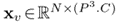

在图2中展示了所提议的模型的概述。UNETR采用收缩-扩展模式,由一堆Transformer组成,编码器通过跳跃连接到解码器。Transformer工作在输入嵌入的一维序列上,这是NLP中常用的方法。同样,将三维输入体积 ,分辨率(H,W,D)和C输入通道划分为平坦的均匀非重叠斑块 ,创建一个一维序列,其中(P, P, P)表示每个patch的分辨率, 为序列的长度。

图2:UNETR架构概述。将一个三维输入体(如MRI图像的C= 4通道)划分为一系列均匀的不重叠的patch,并使用线性层投影到嵌入空间中。该序列与位置嵌入一起添加,并用作Transformer模型的输入。Transformer中不同层的编码表示通过跳跃连接提取并与解码器合并,以预测最终分割。

图1所示:UNETR的概述。提出的模型包括一个Transformers编码器,它直接利用3D patch,并通过跳跃连接 连接到一个基于CNN的解码器。